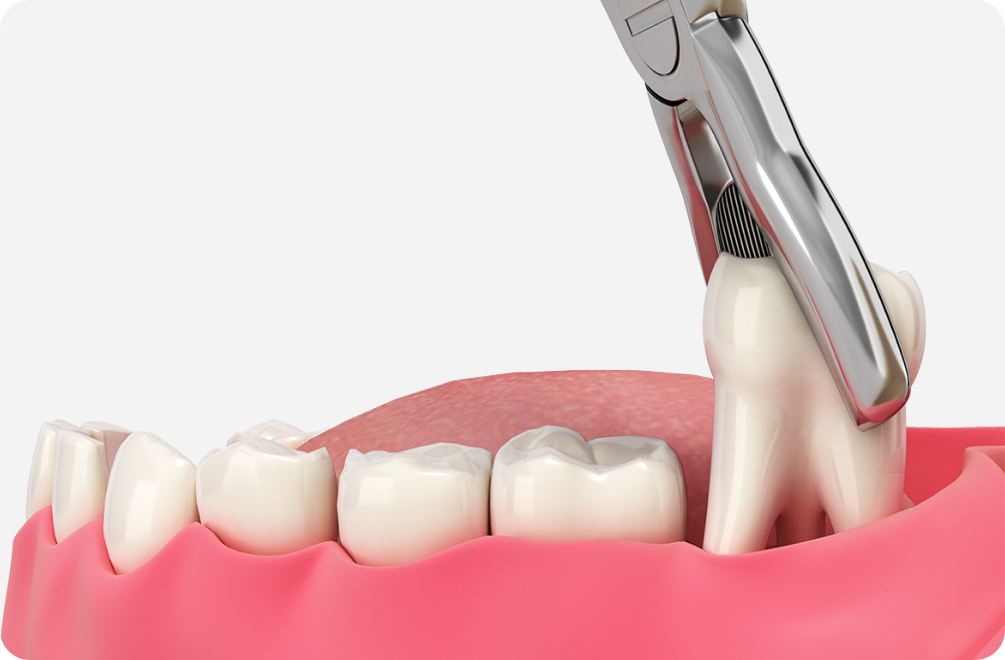

• 수면요법으로 통증 걱정을 덜면서 편안한 '수면 사랑니 발치'

플란치과 수면 사랑니 발치는 의식하진정요법을 활용하여 사랑니 발치에 대한 통증과 두려움을 해소 해 드립니다. 수면마취를 통해 환자분들 가수면 상태로 유도(의식하진정법), 환자분은 사랑니 발치를 진행하는 동안 의식이 있는 상태에서 잠깐 동안 자고 일어난 느낌을 받게 됩니다.

수면 사랑니 발치는 구강악안면외과 전문의가 직접 담당하며 모든 과정은 환자의 안전을 우선으로 하여 진행 됩니다.